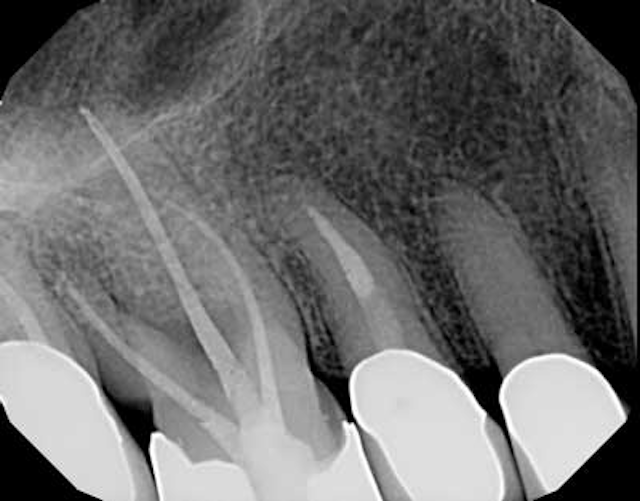

(A) Radiographic evaluation after endodontic treatment. Data are Endodontic Evaluation Cost $620 to $1,472, depending on whether it’s a molar, premolar, or front tooth. There are several steps to a root canal that make up the. Endodontists have advanced training and equipment to perform more. A root canal at an endodontist’s office will cost more than one at a general dentist’s office. During a root canal, your endodontist will thoroughly clean. Endodontic Evaluation Cost.